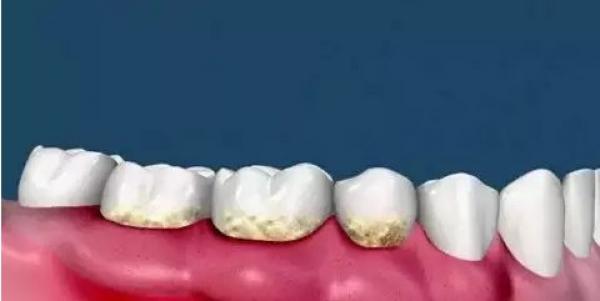

二、牙面上滋生牙菌斑和牙結石。

三、當牙菌斑和牙結石累計一定程度時,牙齦開始變得紅腫。

四、牙菌斑和牙結石沒有被及時的清除,牙齦進一步的紅腫,同時伴有牙齦出血現象。

五、此時在牙齦以下也同樣存在著堅硬的牙結石。

這些牙結石開始刺激牙槽骨的吸收。